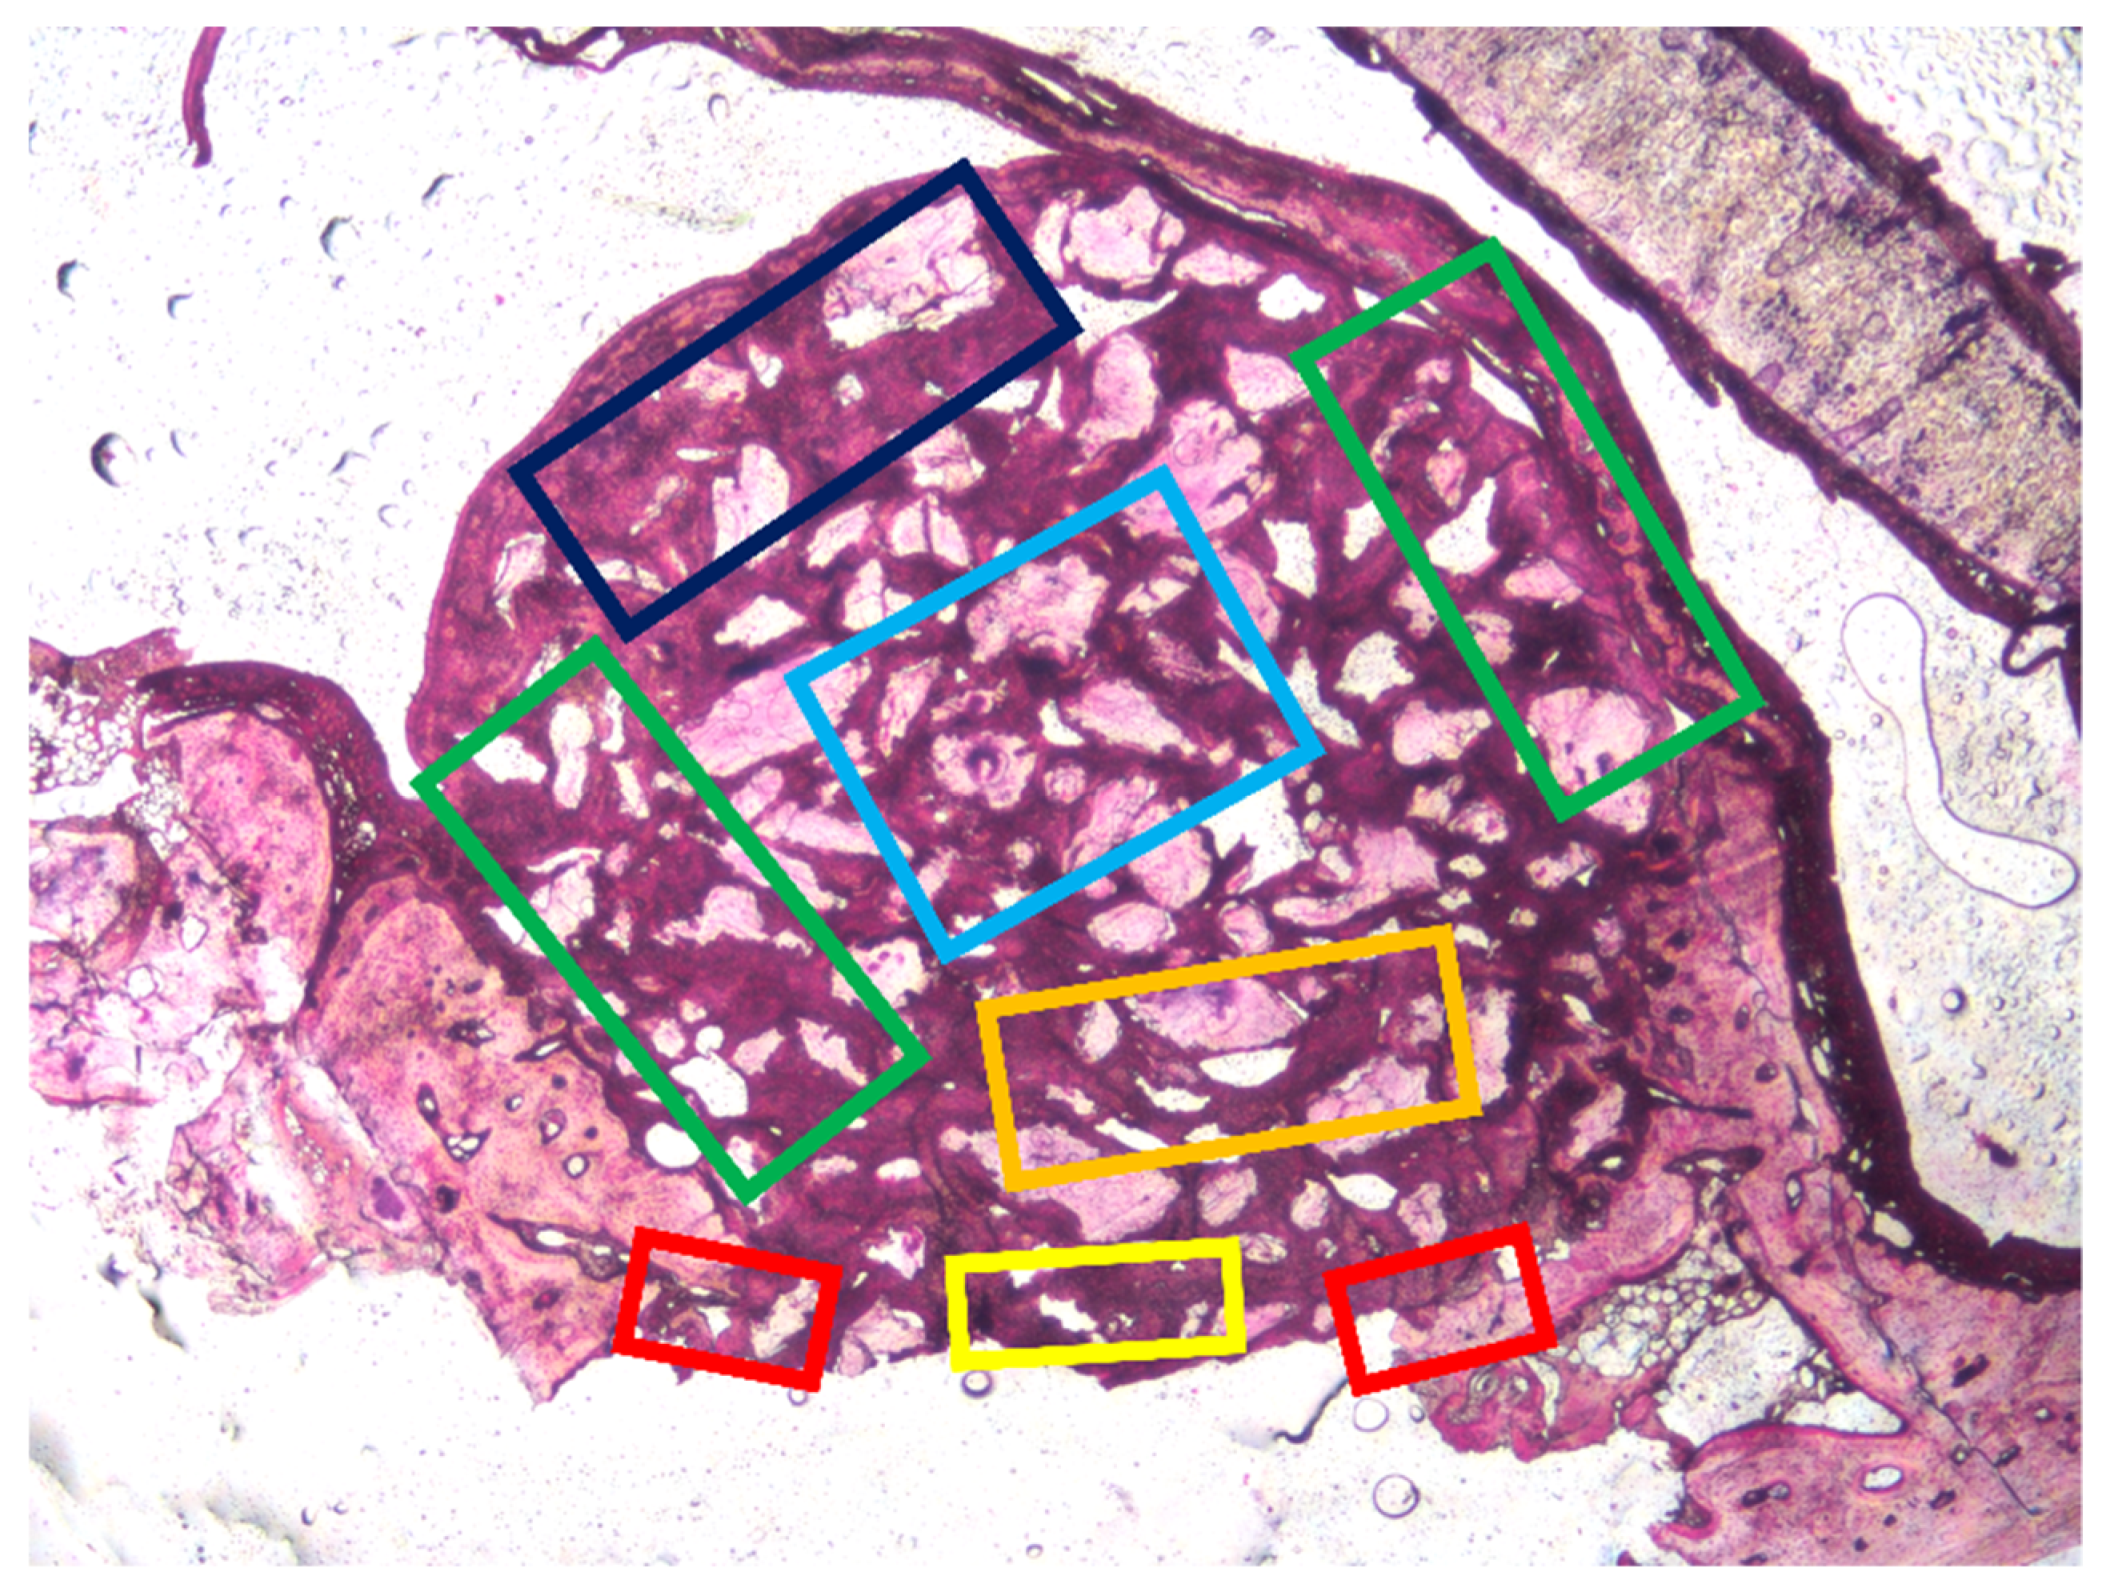

3.1. Grafted Region

3.2. Osteotomy Region